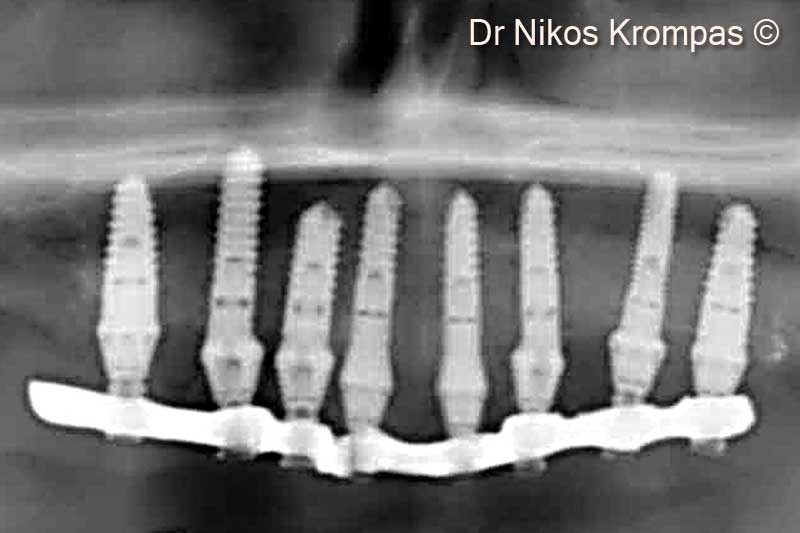

14. 2 years post-op